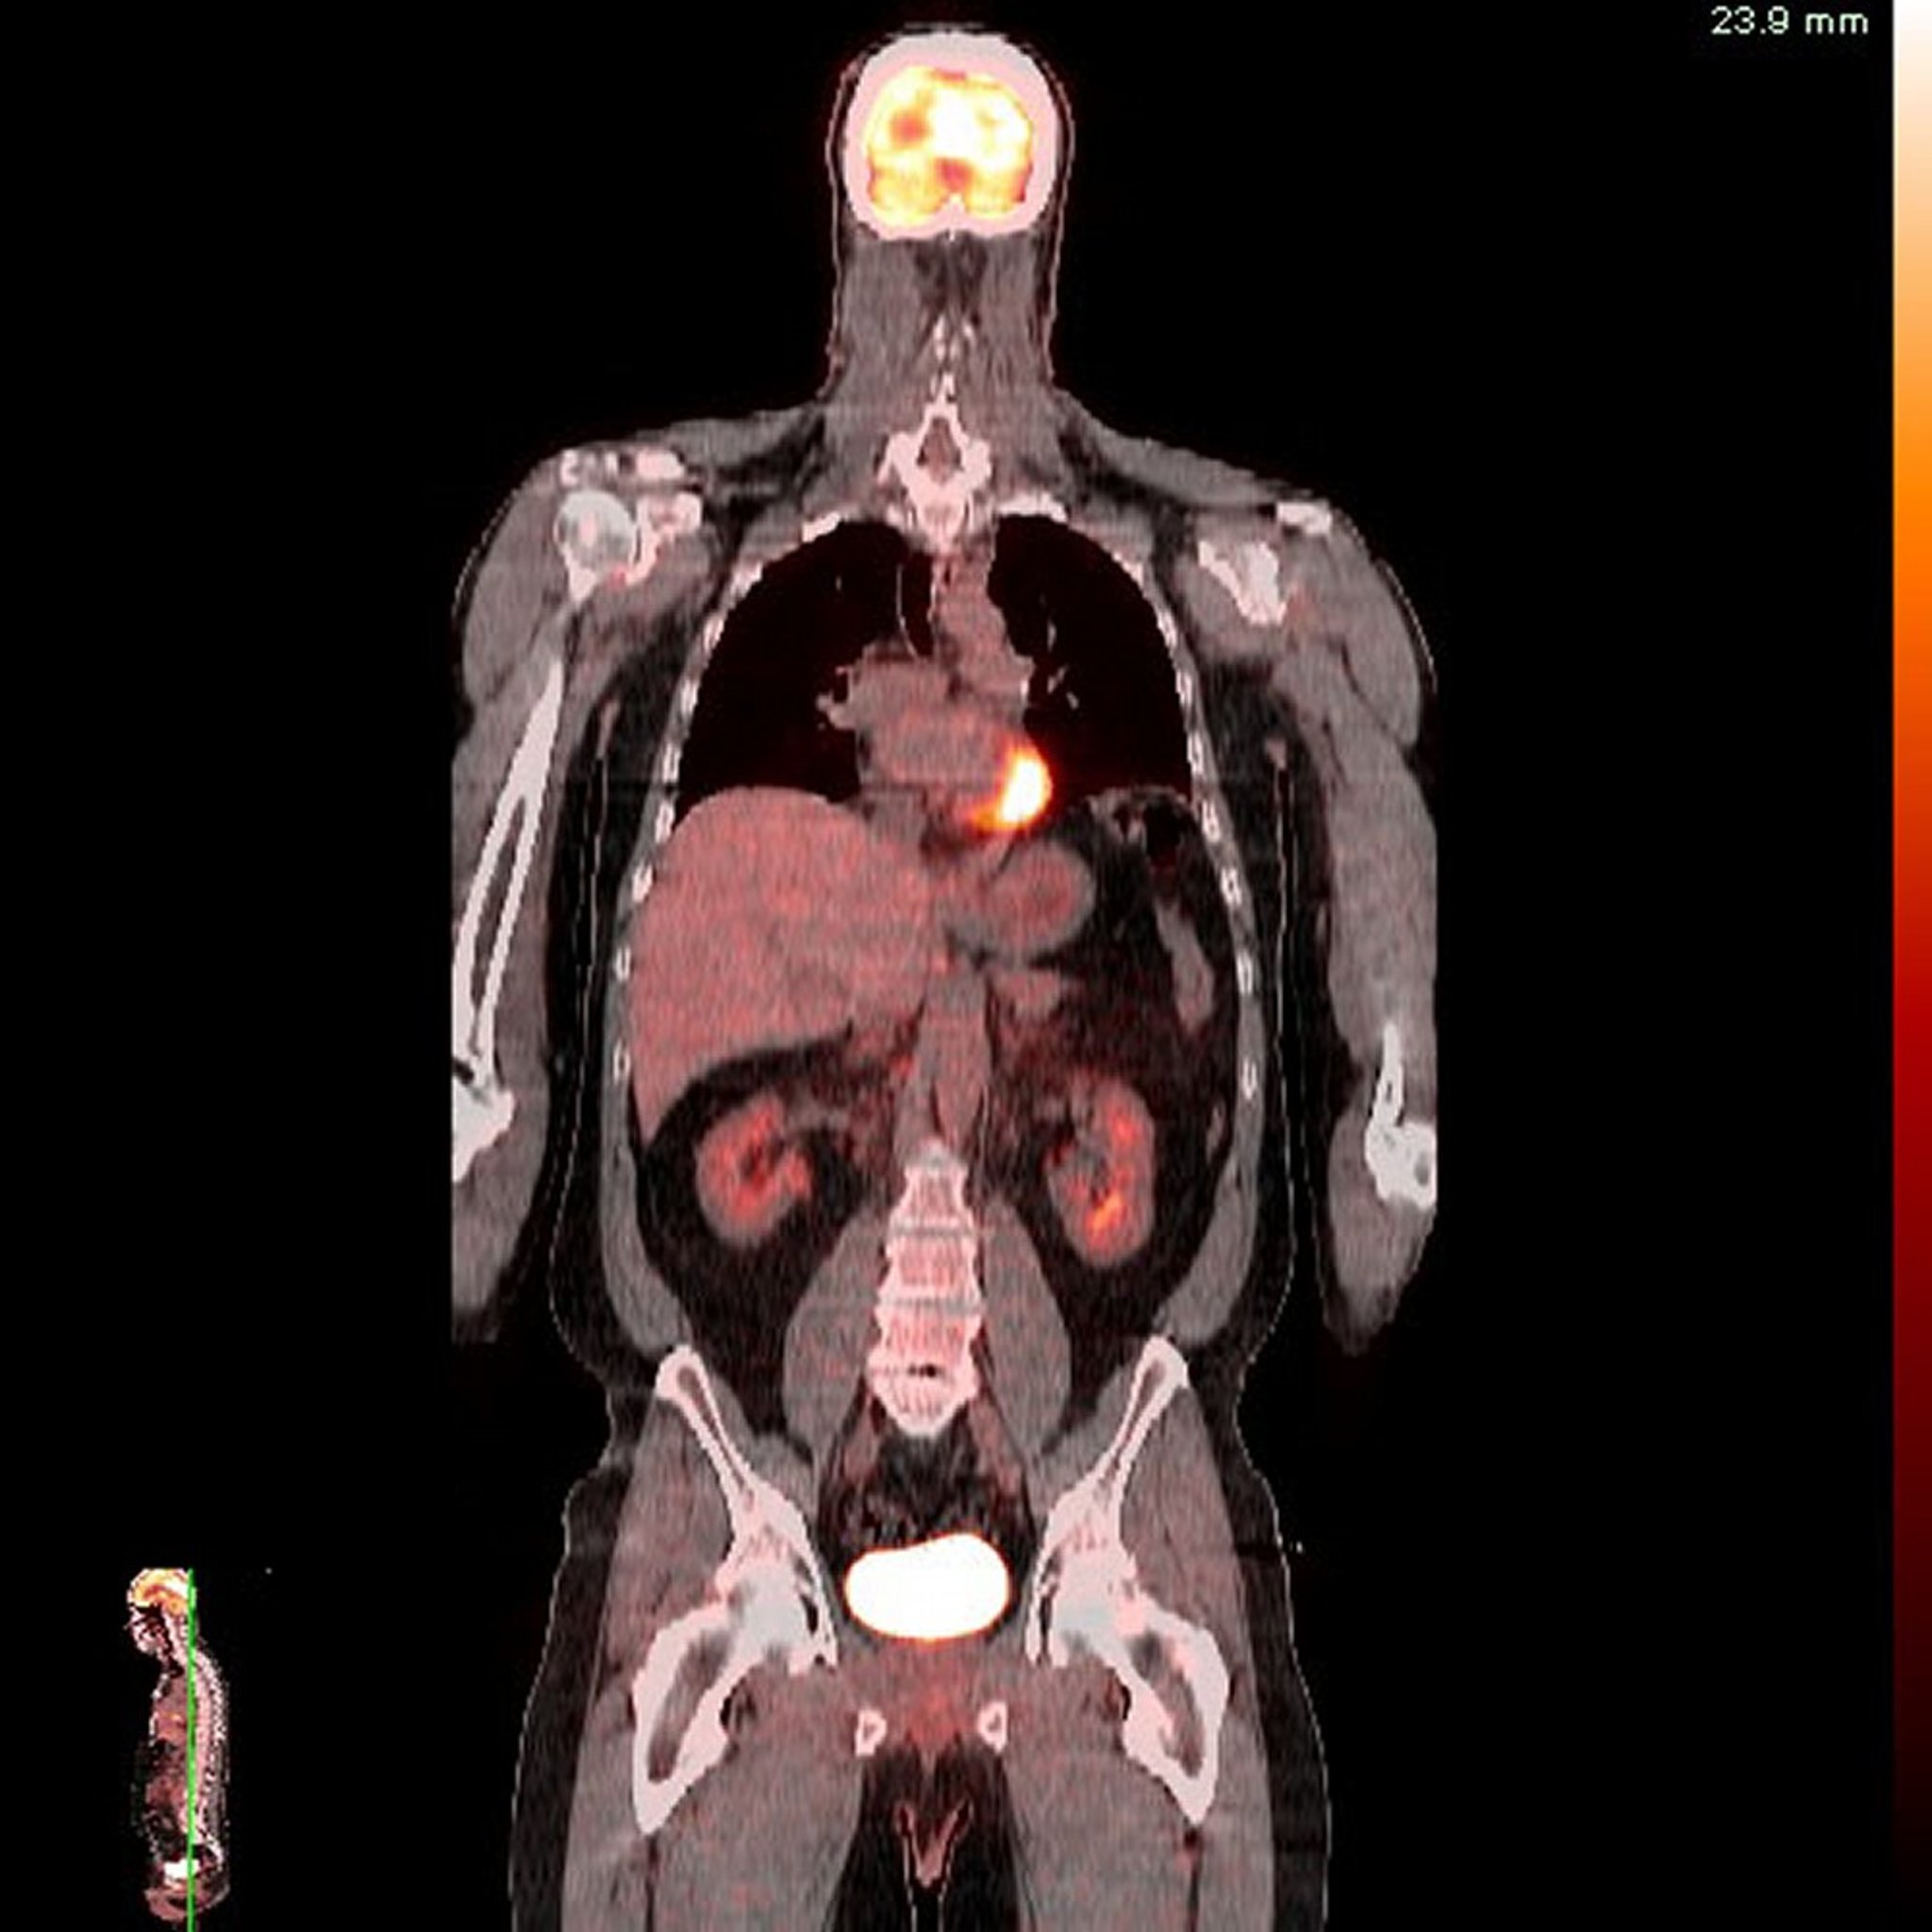

Tomografi Emisi Positron-Tomografi Terkomputasi (PET-CT)

Gambar disediakan oleh Jon A. Jacobson, MD.